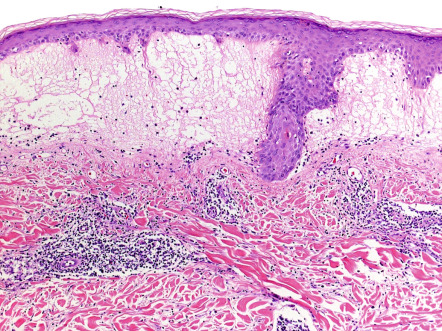

Pathology

There is variable epidermal spongiosis and a superficial and deep, perivascular and periappendageal, lymphohistiocytic dermal infiltrate, often with scattered eosinophils and neutrophils. Significant papillary dermal edema occurs commonly ( Fig. 87.5 ). Rarely, difficulty in distinction from cutaneous lupus may occur if interface changes are significant, or from lymphoma if the dermal inflammatory cell infiltrate is marked.